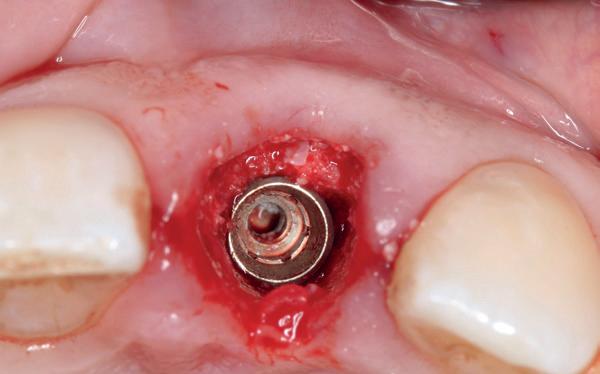

Zes maanden na extractie wordt het implantaat 37 geplaatst. Er is sprake van een goede genezing en de processushoogte en -breedte zijn behouden en opgebouwd. Ook is er zichtbaar gekeratiniseerd weefsel

1 2 Ridge preservation met d-PTFE membranen 35

gewonnen. De wond kan na het plaatsen van een healing abutment primair gesloten worden (Afbeelding 3a-3d).